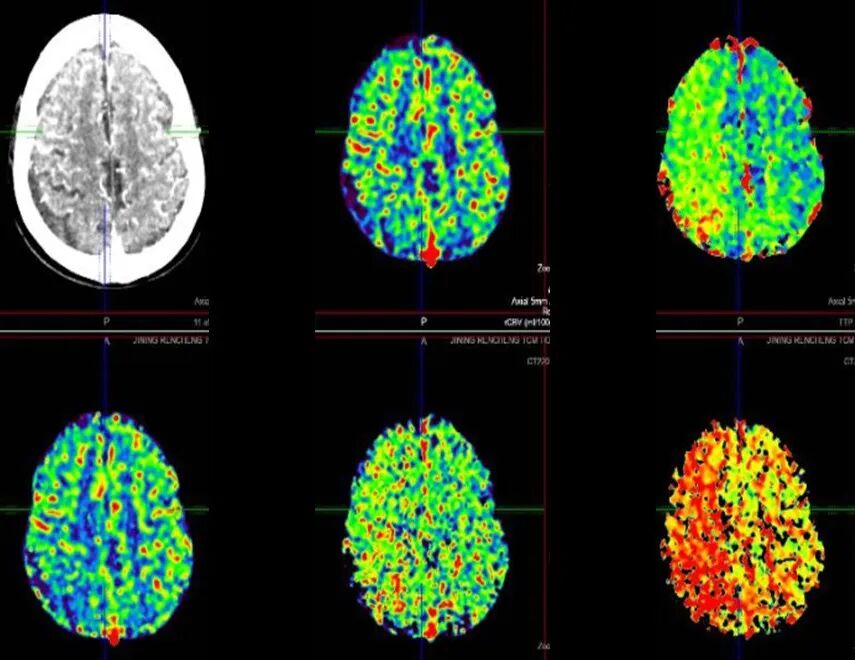

既往病史影像留存

导丝怎么扩【载药时代 球扩天下】NOVA DES®颅内药物洗脱支架在颈内动脉颅内段重度狭窄的应用二例!_https://www.jmylbn.com_新闻资讯_第4张

导丝怎么扩【载药时代 球扩天下】NOVA DES®颅内药物洗脱支架在颈内动脉颅内段重度狭窄的应用二例!_https://www.jmylbn.com_新闻资讯_第5张

2021-6-25 颅脑DWI

2021-6-25 颅脑MRA

导丝怎么扩【载药时代 球扩天下】NOVA DES®颅内药物洗脱支架在颈内动脉颅内段重度狭窄的应用二例!_https://www.jmylbn.com_新闻资讯_第6张

导丝怎么扩【载药时代 球扩天下】NOVA DES®颅内药物洗脱支架在颈内动脉颅内段重度狭窄的应用二例!_https://www.jmylbn.com_新闻资讯_第7张

2021-12-3 DSA

重要影像结论:2021-6-25右侧基底节区新发脑梗死,2021-12-3提示右侧颈内动脉海绵窦段重度狭窄。